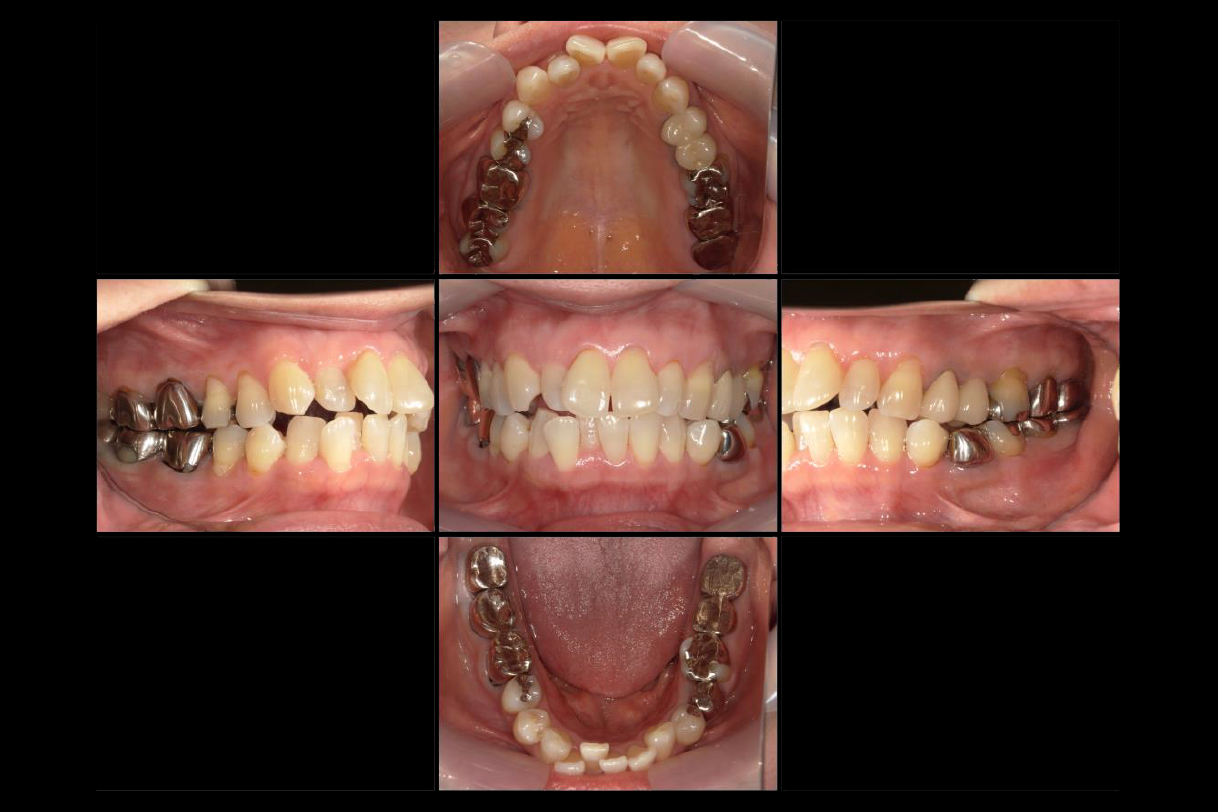

初診時年齢:40代男性

治療:全体矯正

治療法:マウスピース型矯正装置(インビザライン)

治療期間:3年

費用:902,000円(税込)

リスク・副作用:装置装着による違和感、歯の移動時の痛み